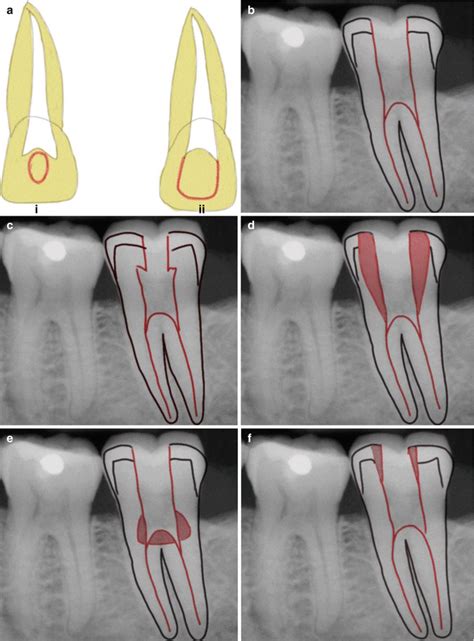

Endodontics Coronal Access Preparation Columbia Ctl